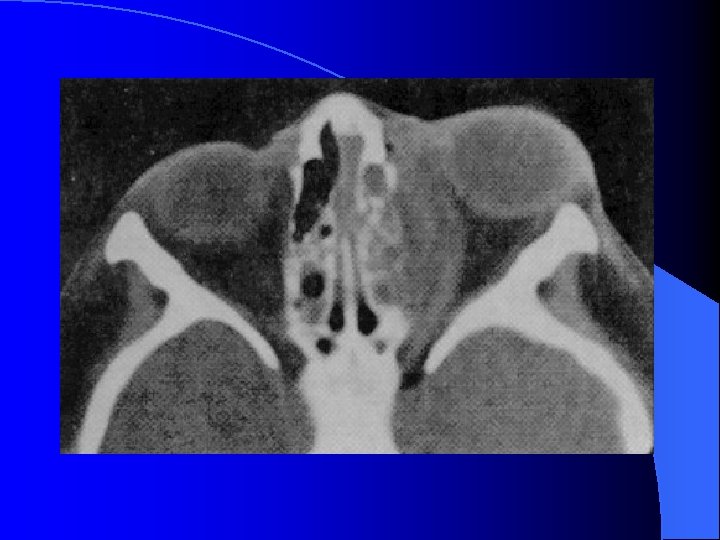

Ethmoïdite aiguë suppurée droite

Forme extériorisée = TDM

MALADIES INFECTIEUSES RHINO SINUSIENNES ETHMOIDITE AIGUË IMAGERIE • Radiographie standard • Echo doppler couleur (opérateur dépendant) • TDM sans et avec injection siège, stade collecté, analyse orbitaire fine